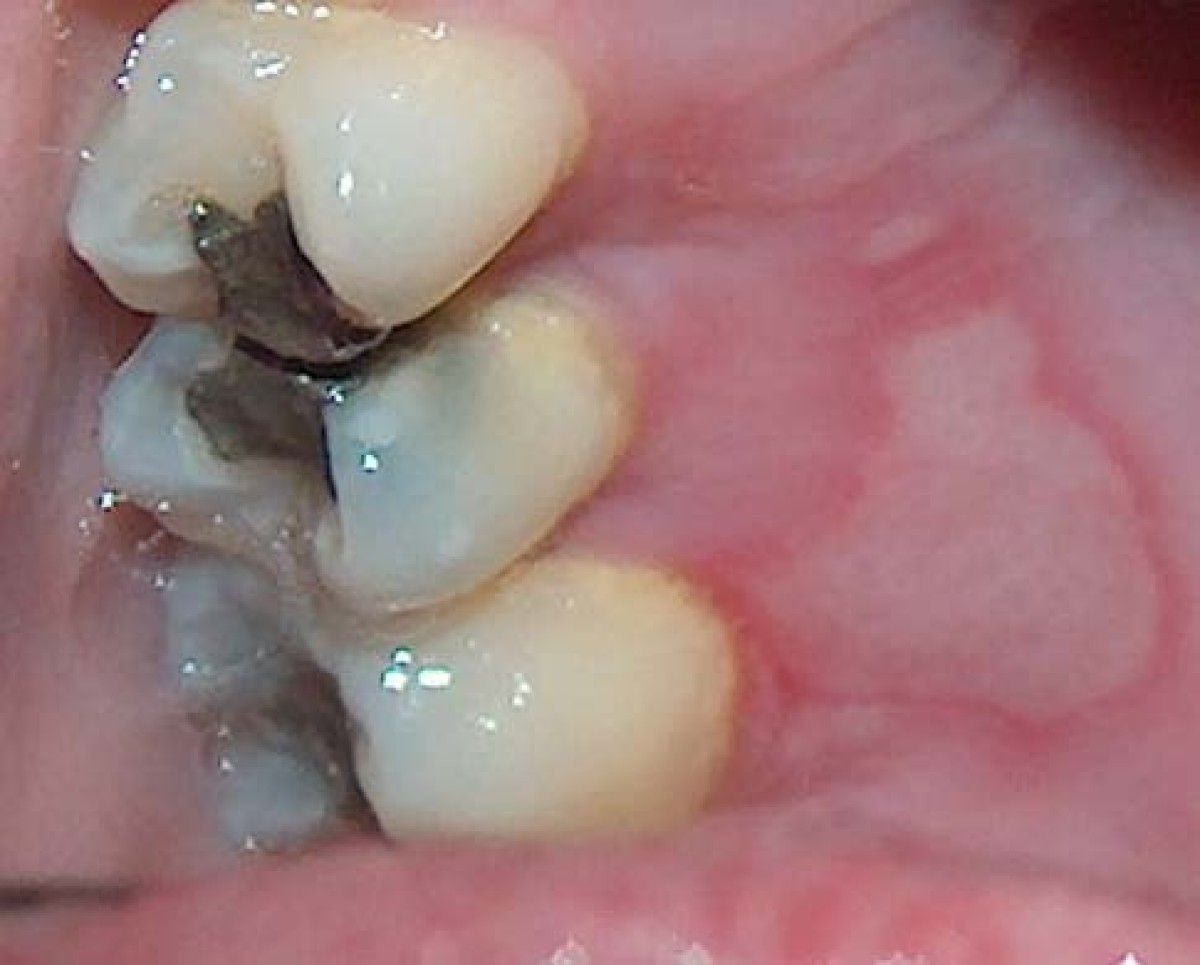

From www.jaci-inpractice.org

Erythematous Candidiasis The Journal of Allergy and Clinical Immunology In Practice Mouth Burning Palate This burning sensation, without an obvious cause, may affect the tongue, gums, lips, cheeks, roof of. Or, the pain may happen with a feeling of numbness, which comes and. Burning mouth syndrome (bms) is a painful, frustrating condition often described as a scalding sensation on the tongue, lips, palate, or. Most often, the pain is on. The main symptom of. Mouth Burning Palate.